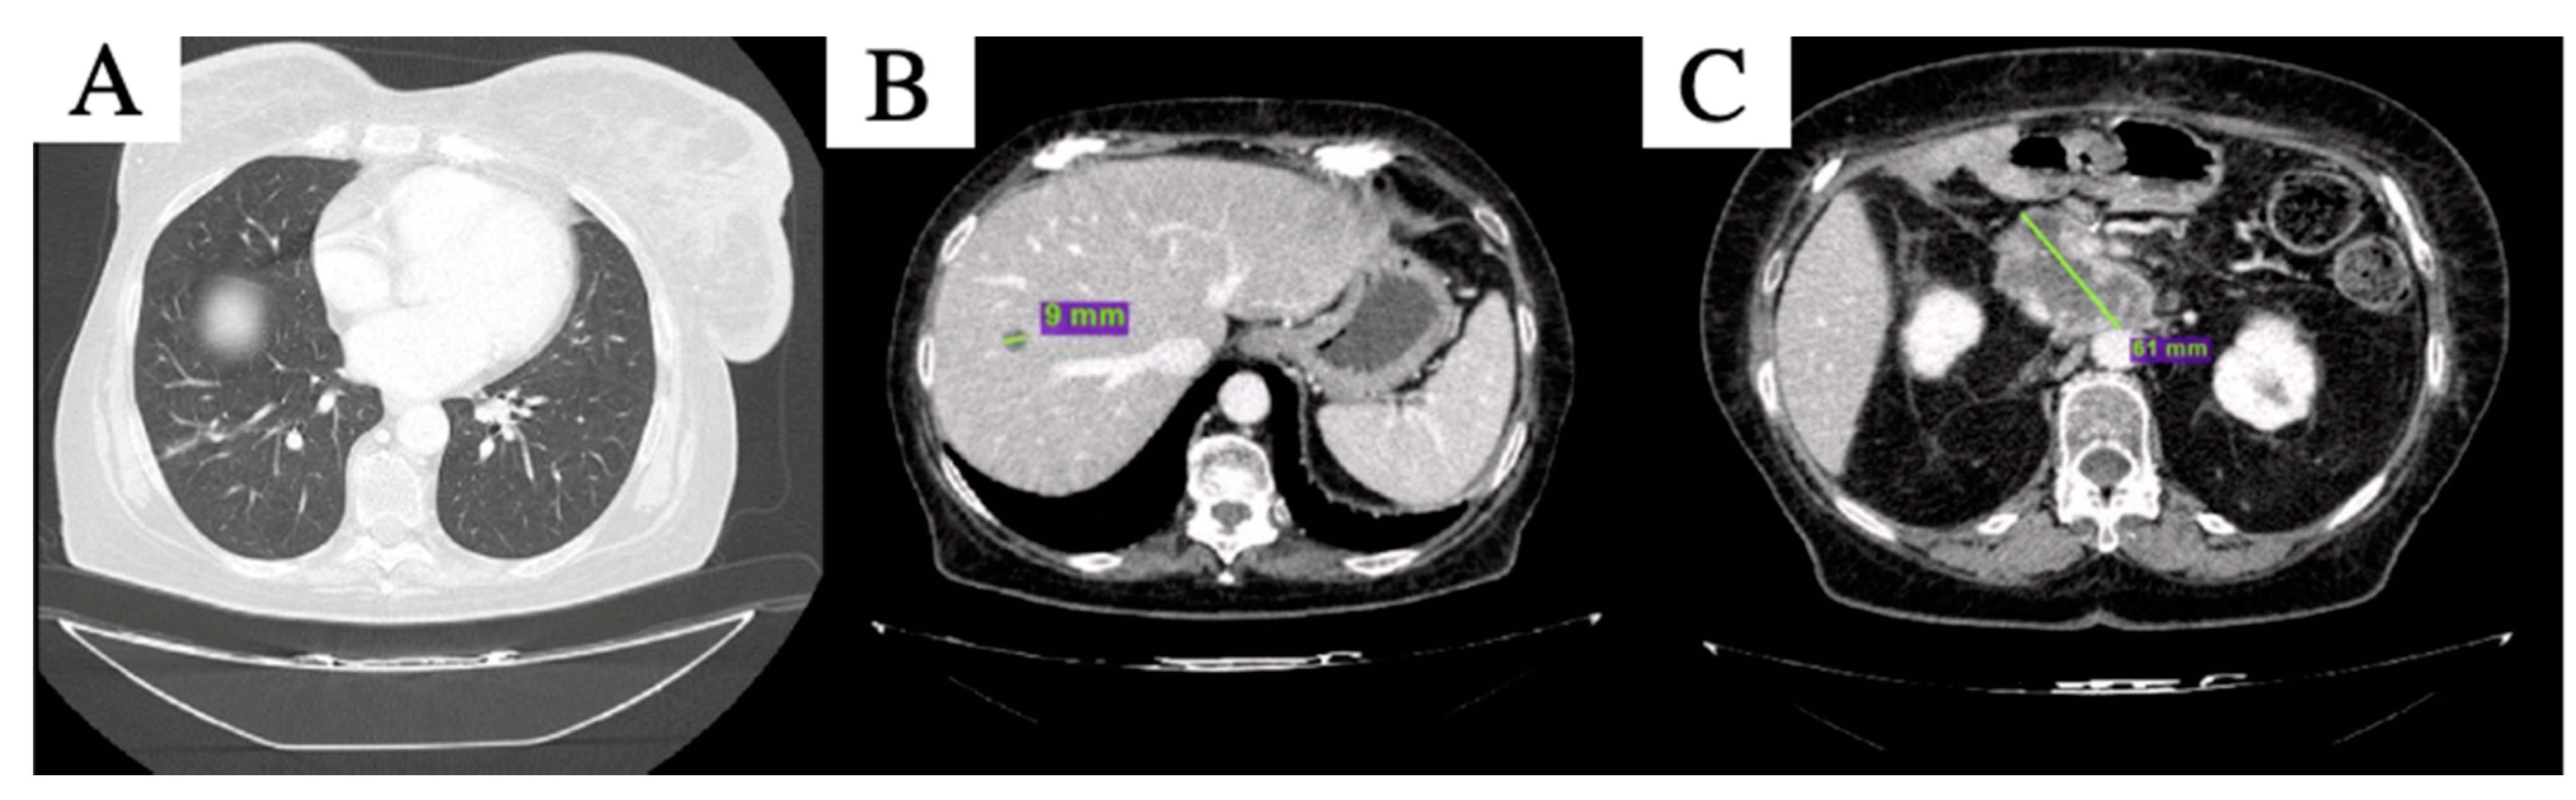

After 4 months of therapy, the new liver lesion was no longer visible; of the other two remaining liver lesions, one reached complete response and the other was further reduced in maximum diameter, while the peripancreatic tissue was stable (Figure 3). Pulmonary lesions were still undetectable, maintaining complete response. Thus, partial response per RECIST 1.1 [12] was declared. The treatment was well tolerated, except for G3 anemia per CTCAE v. 5.0 [13], which required blood transfusions and one level reduction in olaparib dosage after the third cycle, i.e., 200 mg bid capsule. Clinical benefit was also observed, with improved self-care and pain control.

Figure 3.

CT scan after 4 months of olaparib: complete disappearance of the nodular lesioni in inferior lobe of the right lung was confirmed (A), the hepatic lesion in the 8th segment (B) is further reduced in size and peripancreatic tissue is slightly increased and substancial stability of the peripancreatic tissue was described (C).